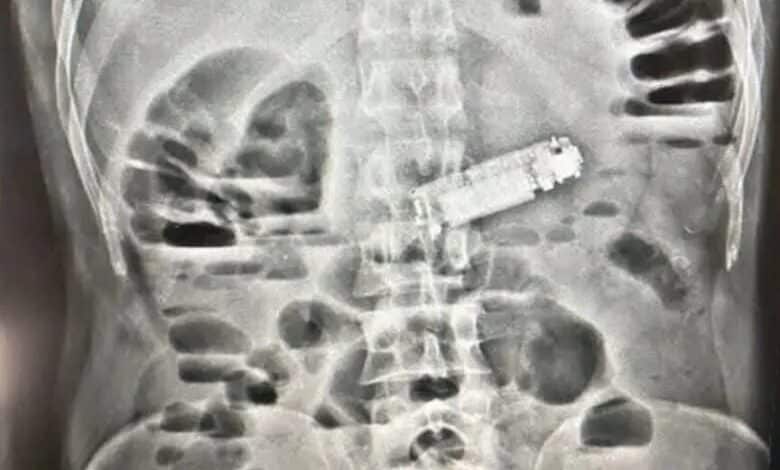

الفحوصات تكشف عن الهاتف داخل معدة المريض

أجرى الفريق الطبي للمريض كافة الفحوصات اللازمة والأشعة التشخيصية، التي أظهرت وجود جسم غريب يعيق عمل المعدة، ليتبين أنه هاتف محمول تسبب في انسداد فتحة البواب، وهو ما كان وراء الأعراض الخطيرة التي يعاني منها المريض